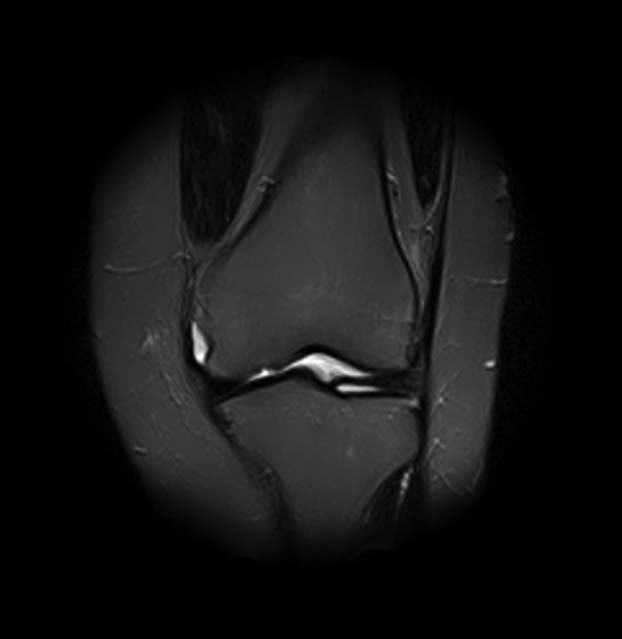

добрый день! Не очень понятен принцип, по которому отбирались снимки МРТ. Большинство из них не показательны. Вижу пока только повреждение хряща на феморопателлярной поверхности. Хлтелось бы посмотреть диск целиком

На снимках повреждений наружного мениска не вижу и кисты мениска не вижу. Есть повреждение хряща на передней поверхности внутреннего мыщелка бедра. Вполне может оказаться, что повреждение лоскутное. А какая консервативная терапия проводилась?